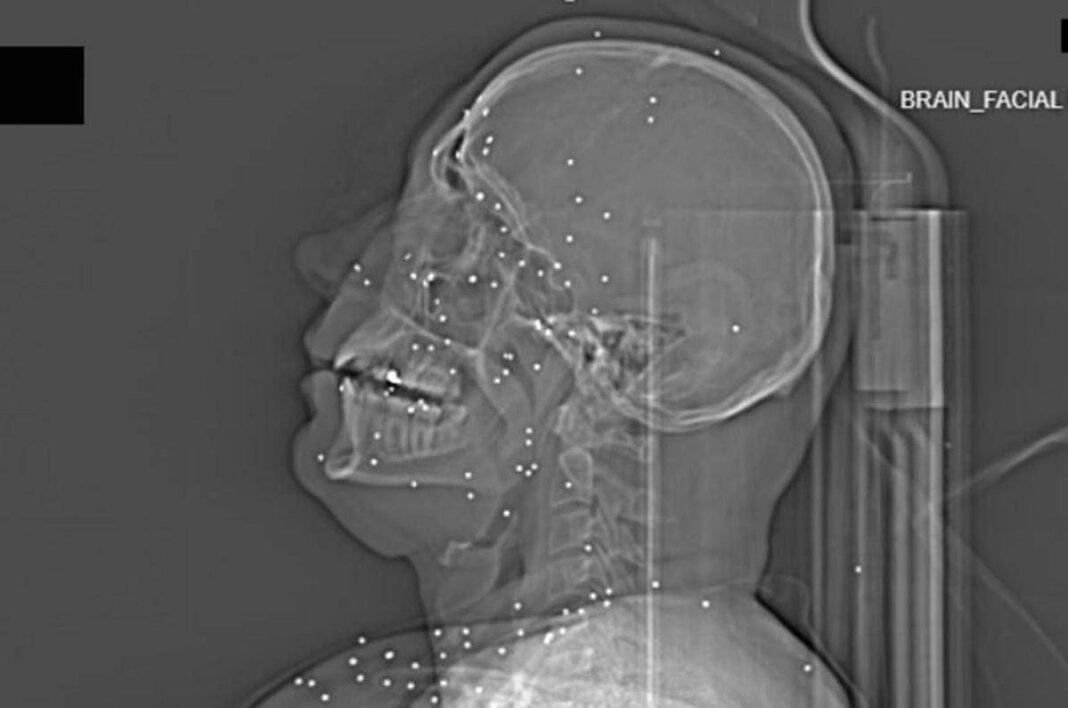

Il volto di Anahita – nome di fantasia, poco più che ventenne – appare come un cielo notturno attraversato da punti luminosi. Piccole sfere metalliche, da 2 a 5 millimetri, disseminate sul viso, nelle orbite oculari, persino nella massa scura del cervello. Sono proiettili “birdshot”, pallini da caccia sparati da un fucile a pompa. A distanza ravvicinata, spiegano gli esperti, non sono affatto “meno letali”: possono frantumare ossa, devastare tessuti molli, perforare facilmente un bulbo oculare. Anahita ha perso almeno un occhio, forse entrambi.

Quell’immagine non è un caso isolato. Fa parte di oltre 75 set di esami diagnostici provenienti da un singolo ospedale di una grande città iraniana, raccolti nel corso di una sola serata, durante la stretta repressiva di gennaio. Una concentrazione temporale che, già di per sé, racconta una dinamica da “mass casualty”, evento con numerose vittime simultanee, tipico degli scenari di guerra o dei grandi disastri.

Le valutazioni, condotte congiuntamente dal Guardian e dalla piattaforma di fact-checking Factnameh, sono state affidate a un panel indipendente di specialisti internazionali: medici d’urgenza, radiologi, esperti di trauma imaging e balistica. Un ex medico iraniano di pronto soccorso, anch’egli consultato, ha confermato la coerenza del software utilizzato per gli esami e l’assenza di segni di manomissione. Gli esperti precisano che, senza cartelle cliniche complete, non è possibile formulare diagnosi definitive sui singoli pazienti. Ma il quadro complessivo, spiegano, è inequivocabile.

Accanto ai colpi di grosso calibro, emerge con forza un altro elemento: l’uso sistematico dei pallini metallici. L’Iran è tra i pochi Paesi in cui le forze di sicurezza impiegano birdshot metallico. A lunga distanza, i pallini si disperdono e colpiscono indiscriminatamente. A distanza ravvicinata, diventano devastanti: decine, talvolta centinaia di micro-proiettili che penetrano simultaneamente nei tessuti.

Ma non è solo la gravità delle ferite a colpire. Caso dopo caso, le immagini mostrano corpi colpiti al volto, al torace, ai genitali. Ventinove pazienti risultano feriti al viso da birdshot. Almeno nove presentano lesioni nell’area genitale o pelvica, provocate sia da pallini sia, in alcuni casi, da fucili ad alto calibro.